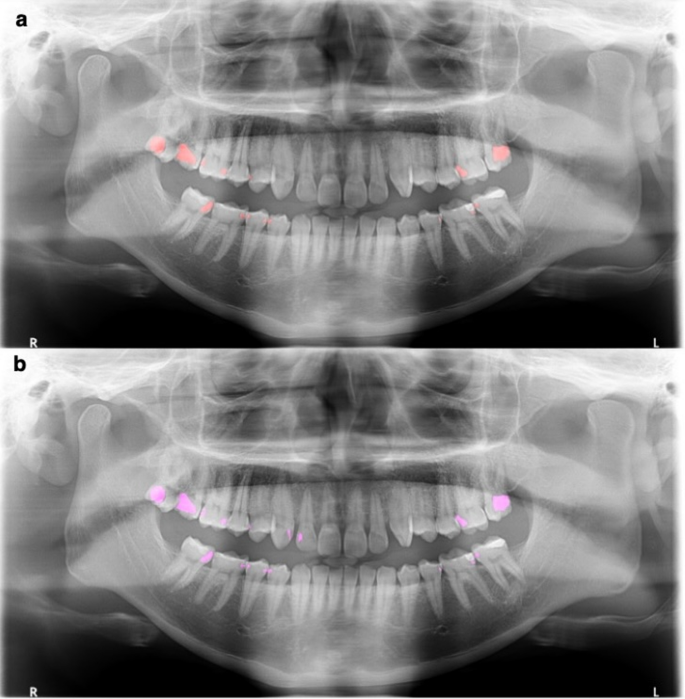

The caries detection system relies on semantic segmentation within image processing techniques. It operates by taking a panoramic radiograph as input and classifying and segmenting the regions of detected caries pixel by pixel. The process involves applying a tooth detection model to the panoramic radiograph to identify individual teeth. The model delineates the boundary of each tooth within the panoramic radiograph, subsequently extracting each tooth into a separate image. These separated tooth images are then input into the caries segmentation model to identify the caries regions. Once the caries regions are determined, the resulting segmented map is overlaid onto the separated tooth images and then reassembled to visualize a predicted panoramic radiograph (Fig. 2).

Agreement of tooth number with dental caries on panoramic radiograph

An analysis comparing AI caries segmentation to oral and maxillofacial radiologists (ground truth) revealed strong agreement (weighted kappa = 0.943, 95% confidence interval [CI]: 0.927–0.958) between the two methods (Italic number, Table 2). The most frequent agreement involved both AI and radiologists identifying two teeth with caries per case (123 cases), followed by the identification of three teeth with caries per case (75 cases). Figure 3 shows an example of 13 posterior teeth with dental caries. The upper image displays the ground truth segmentation, labeled by an oral and maxillofacial radiologist, while the lower image presents the AI model’s segmentation, perfectly matching the ground truth for all 13 caries. However, discrepancies existed in 56 cases (11.2% of all evaluated cases). These disagreements are Bold and Underline numbers in Table 2. Notably, in most disagreements, the radiologist identified one more tooth with caries than the AI system. The most significant discrepancy involved a ground truth evaluation of five teeth with caries, while the AI system identified only two (Underline number, Table 2).